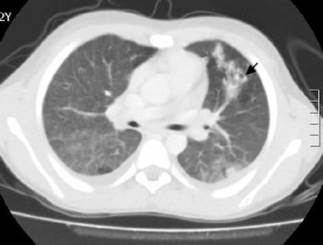

The Doppler ultrasound of the lower limb showed thrombosis of the external iliac and left common femoral veins (Figures 2 and 3). The chest x-ray, performed due to suspicion of septic pulmonary embolism, showed acinar nodule lesions (Figure 4). The CT scan showed pulmonary and subpleural nodules (Figure 5), and a D-dimer value of200-00 ng/dL was determined (reference <200). Consequently, it was confirmed that the patient had venous thromboembolism and septic pulmonary embolism. Echocardiogram and abdominal ultrasound were normal. The treatment with oxacillin was continued and the new blood cultures, taken after five days, were negative. The patient completed 42 days of antibiotic and anticoagulant treatment, and was discharged with satisfactory evolution.

CT scan with cavitating lung nodules (black arrow).

Figure 5: CT scan with cavitating lung nodules (black arrow).

Source: Document obtained during the study.

Likewise, in a patient presenting with staphylococcemia with acute respiratory distress, septic pulmonary embolism associated with deep vein thrombosis of the limbs should be suspected, since it may occur in up to 65% of cases. Computerized axial tomography helps to diagnose pulmonary involvement by thromboembolism. 12